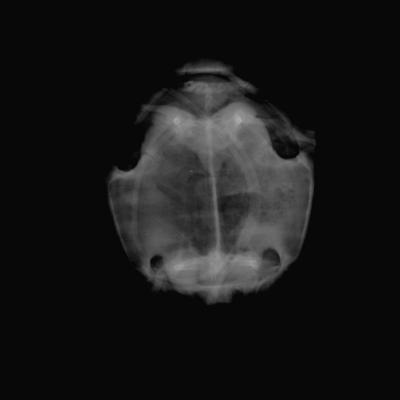

Tortue